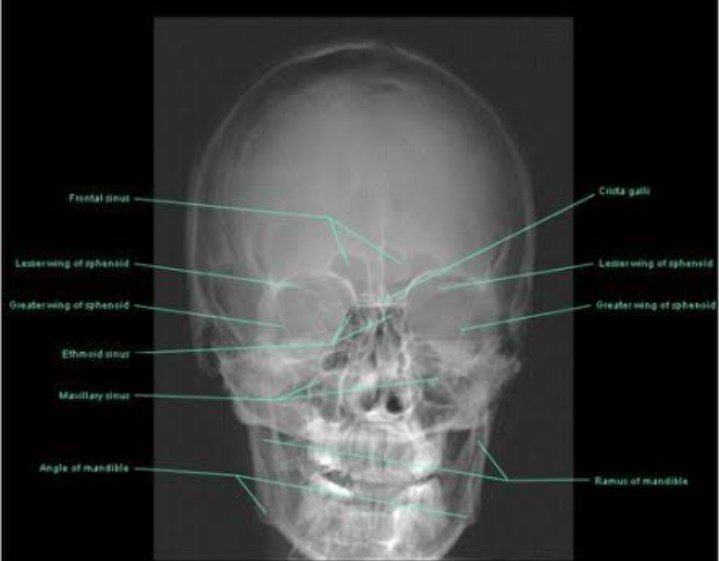

Anatomy / Dental Histology / Histology / Oral Medicine And Radiology / Pathology / Physiology / Uncategorized normal radiographic anatomical landmark of maxilla and mandible LinkJune 9, 2021February 24, 2023 dr swati mandhanLeave a comment Adobe Scan Jun 09, 2021.pdfDownload Share this:Tweet Share on Telegram (Opens in new window) Telegram Share on WhatsApp (Opens in new window) WhatsApp Email a link to a friend (Opens in new window) Email Like Loading... Related